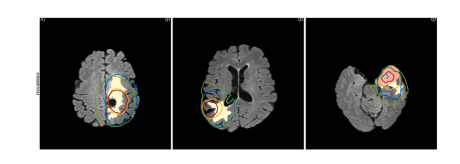

Fig. 7. Parameter estimation results for patients P1–P8 using SEG. (A) Pre-operative T1Gd. (B) Pre-operative FLAIR. © Superposition of predicted tumor cell density 𝑢 𝐹𝐷𝑀 onactual segmentations: WT (yellow line) and TC (red line). (D) Superposition of predicted tumor cell density 𝑢 𝐹𝐷𝑀 on registered atlas with 𝜕𝛺 (orange line). (E) Overlap of inferredsegmentations: 𝑢 W 𝑐 T (yellow line) and 𝑢 TC 𝑐 (red line) on actual segmentations: WT (beige fill) and TC (pink fill); Margins for CTV RTOG (green) and CTV P (blue). (F) Tumor recurrence,compared with margins for CTV RTOG (green) and CTV P (blue). (G) 3D reconstructions of CTV P an

图7:使用SEG数据对患者P1至P8进行参数估计的结果。(A) 术前T1钆增强(T1Gd)图像。(B) 术前液体衰减反转恢复(FLAIR)图像。© 预测的肿瘤细胞密度(u{FDM})与实际分割结果的叠加:全肿瘤(WT,黄线)和肿瘤核心(TC,红线)。(D) 预测的肿瘤细胞密度(u{FDM})与配准后的图谱以及边界(\partial\Omega)(橙线)的叠加。(E) 推断的分割结果的重叠情况:(u{WcT})(黄线)和(u{TCc})(红线)与实际分割结果:全肿瘤(米色填充区域)和肿瘤核心(粉色填充区域);放射治疗肿瘤协作组(RTOG)的临床靶区(CTV)边界(绿色)和个性化临床靶区(CTV P)边界(蓝色)。(F) 肿瘤复发情况,与放射治疗肿瘤协作组(RTOG)的临床靶区(CTV)边界(绿色)和个性化临床靶区(CTV P)边界(蓝色)进行比较。(G) 个性化临床靶区(CTV P)的三维重建。